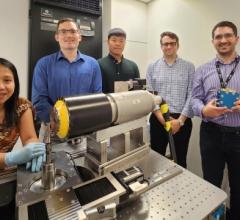

March 22, 2023 — A novel imaging modality that can visualize the distribution of medical radiopharmaceuticals with very ...